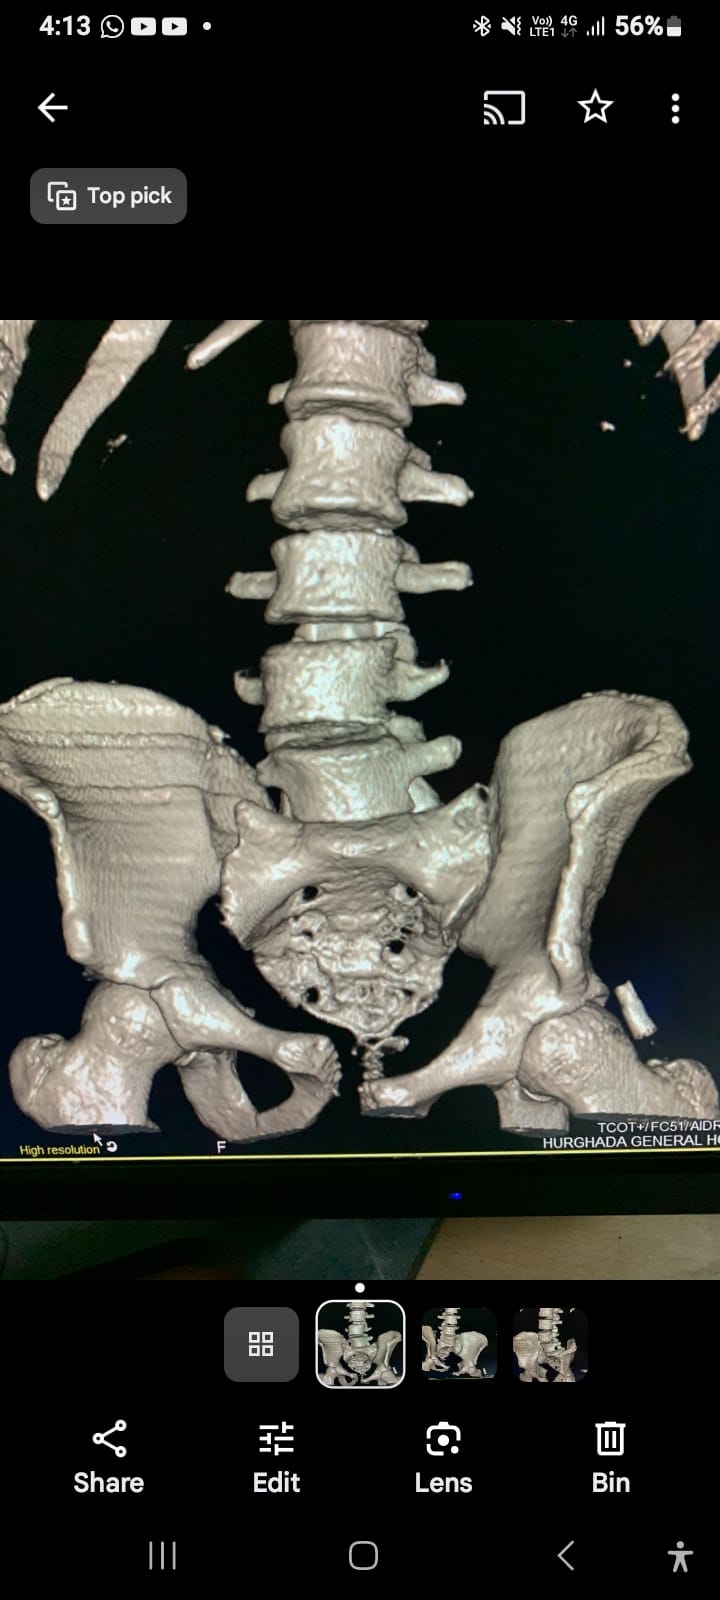

ياسين محمد أمين العمر:١٧ عامًا اصيب بكسر غير ثابت متفتت بالحوض يناير ٢٠٢٣